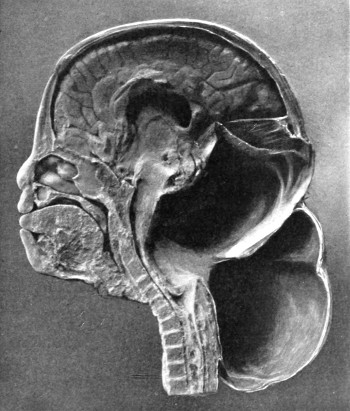

Fig. 2. Cranio-cerebral Topography. 1, 1, Reid’s base-line; 2, 2, A line parallel to the above at the level of the supra-orbital margin; 3, The middle meningeal artery; 4, The anterior branch; 5, 5, 5, The three sites for trephining; 6, The posterior branch; 7, The site for trephining; 8, The point for trephining to reach the descending horn of the lateral ventricle; 9, The lateral sinus; 10, The inion; 11, The mastoid process; 12, Macewen’s suprameatal triangle; 12a, The mastoid antrum; 12b, The facial nerve; 13, The suprameatal and supramastoid crests; 14, 14, The temporal crest; 15, The temporal fossa; 16, The external angular frontal process; 17, The tendo-oculi attachment; 18, The lachrymal groove. (Reproduced, by the permission of Mr. H. K. Lewis, from the author’s work on ‘Landmarks and Surface-markings’.)

This artery is given off from the internal maxillary; after a short extra-cranial course it enters the skull through the foramen spinosum, and soon divides into two main terminal branches. The site of division corresponds to a point situated just above the centre of the zygoma.

The anterior branch passes at first in a forward and upward direction towards the anterior inferior angle of the parietal bone, and then turns upwards and backwards towards the vertex of the skull. The main ‘danger zone’ in the course of this vessel may be mapped out by taking points which lie respectively 1, 11⁄2, and 2 inches behind the external angular frontal process and an equal distance above the upper border of the zygoma. A line uniting these three points represents that part of the anterior division of the middle meningeal artery which is most liable to injury and which therefore most frequently requires exposure.

The uppermost point may, however, be regarded as the ‘site of election’ for exposure of the artery, as, in trephining over either of the two lower points, difficulty may be experienced in the removal of the disk of bone, since the posterior border of the great wing of the sphenoid tails off on to the anterior inferior angle of the parietal bone in such a manner that to effect a clean removal of the disk is often impossible. Another disadvantage to trephining low down lies in the fact that in about 30 to 40 per cent. of cases the artery occupies, in that situation, a canal in the bone.

The posterior branch passes almost horizontally backwards, parallel to the zygoma and supramastoid crest, towards the posterior inferior angle of the parietal bone. The vessel can readily be exposed[6] by trephining over the point at which a line drawn backwards from the upper border of the orbit, parallel to Reid’s base-line,[1] cuts another line directed vertically upwards from the posterior border of the mastoid process.

Both branches of the middle meningeal artery possess important relations to the cortex cerebri, the anterior branch passing upwards in relation to the precentral or motor area, traversing, from below upwards, the motor speech area (on the left side of the head), the centres for the movements of the face, upper extremity, trunk, and lower extremity. The posterior branch, on the other hand, passes backwards in relation to the temporo-sphenoidal lobe, one of the so-called ‘silent areas’ of the brain. Throughout their course the middle meningeal vessels lie between the dura mater and the bone.

The lower limit of the cerebrum can be mapped out in the following manner: From a point situated about 1⁄2 inch above the nasion a line is drawn outwards which follows the curve of the upper border of the orbit as far as the external angular frontal process, thence curving upwards and backwards to the Sylvian point (see below). The temporo-sphenoidal lobe sweeps forwards to the posterior border of the malar bone, and its lower limit lies practically flush with the upper margin of the zygoma. At and behind the ear the lower limit of the cerebrum corresponds to the suprameatal and supramastoid crests, subsequently following the curve of the lateral sinus from the mastoid process to the external occipital protuberance.